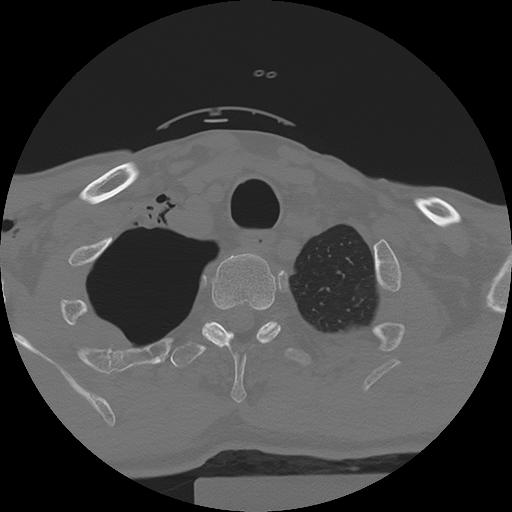

11 HUESO,,Axial,2.0,HUESO,,